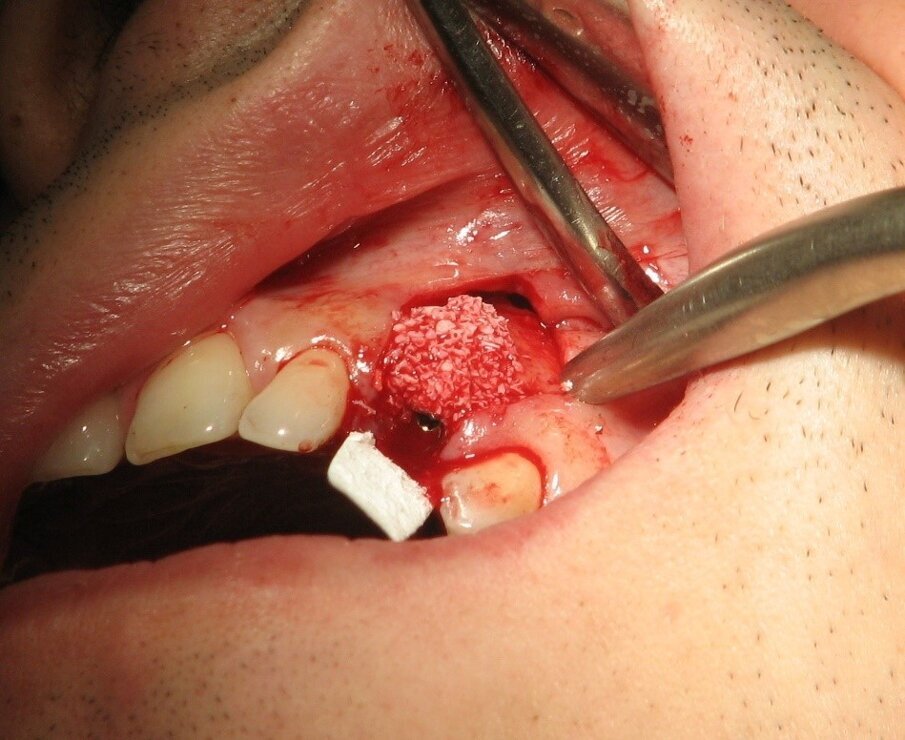

Posebnu pažnju treba posvetiti minimalno traumatskoj ekstrakciji zuba. Upotreba neke od regenerativnih procedura često prati imedijatnu ugrandju implantata i od izuzetne je važnosti odabrati odgovarajuću proceduru za svakog pacijenta.

Komplikacije imedijatne ugradnje implantata su brojne i prvenstveno su uslovljene neadekvatnim odabirom slučaja i planom terapije. Estetski neuspesi implantata u frontalnim regijama predstavljaju jednu od najtežih komplikacija u savremenoj implantologiji. Razlozi za nastanak ovih komplikacija su: traumatska ekstrakcija zuba, nepravilno pozicioniranje implantata, neodgovarajući dijametar implantata, neadekvatna upotreba regenerativnih tehnika za nadoknadu koštanog i mekog tkiva kao i izrada neodgovarajućih protetskih nadoknada.